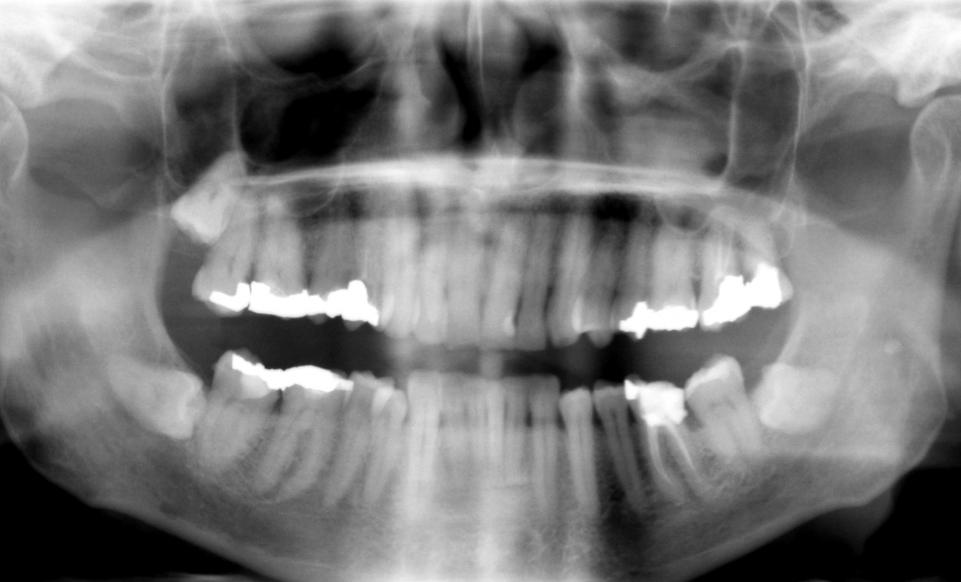

The tooth filling works by stimulating stem cells to encourage dentin growth. This is the bony material which makes up the majority of the tooth. Therefore, patients can effectively regrow teeth damaged through dental disease. Compared to the current methods used to treat cavities, this might sound great to anyone with a fear of the dentist.

Aside from a less traumatic experience in the chair, there are many benefits of this type of dentistry. “Existing dental fillings are toxic to cells and are therefore incompatible with pulp tissue inside the tooth,” said Adam Celiz, a research fellow from the University of Nottingham. “In cases of dental pulp disease and injury a root canal is typically performed to remove the infected tissues.”

Celiz describes the process, “We have designed synthetic biomaterials that can be used similarly to dental fillings but can be placed in direct contact with pulp tissue to stimulate the native stem cell population for repair and regeneration of pulp tissue and the surrounding dentin.”